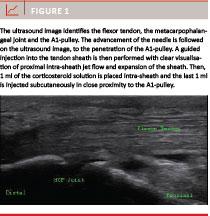

The corticosteroid injections will be ultrasound-guided using a Mindray M7 (Mindray Medical Int. Ltd.) with a linear array transducer and performed at 12 MHz. The patient is seated opposite the physician with the hand resting on a table, palm upwards, fingers pointing to the physician. The area of the affected A1-pulley is prepared, in plenty, with an aqueous solution containing ethanol 85% vol., which is used both as an antiseptic measure and as the connecting media between the skin and the transducer. The transducer in now placed in the long-axis direction on the volar side of the affected finger identifying the flexor tendons in the full length of the ultrasound image to ensure proper mid-axial alignment. The metacarpophalangeal joint is to be seen at the distal end of the image (see Figure 1). A corticosteroid solution containing 1 ml of triamcinolonacetonid 40 mg/ml (Kenalog, Bristol-Myers Squibb AB) and 1 ml of lidocaine 10 mg/ml is prepared in a syringe mounted with a 23G blue needle. A mid-axial, palmar access by non-touch technique, just distally to the metacarpophalangeal joint, is used for needle penetration in the skin. The advancement of the needle is followed in the ultrasound image to the penetration of the A1-pulley. A guided injection into the tendon sheath is now performed. When performed correctly clear visualisation of proximal intra-sheath jet flow and expansion of the sheath is seen. If this is not seen or resistance is felt during injection, this indicates intra-pulley or intra-tendon location of the needle. The position of the needle is then altered slightly as appropriate to achieve visualisation of jet-flow and expansion of the sheath. After placement of 1ml of the corticosteroid solution, the needle is withdrawn just superficially to the A1-pulley, and the last 1ml is injected subcutaneously in close proximity to the A1-pulley. The needle is now fully withdrawn. Aspiration is performed when passing through the layer of dermis to minimize iatrogenic skin reactions. A simple Band-Aid is applied. The patient is informed to keep the finger still for the next 24 h to minimize the risk of immediate “wash-out”, after which no further restrictions are implemented.